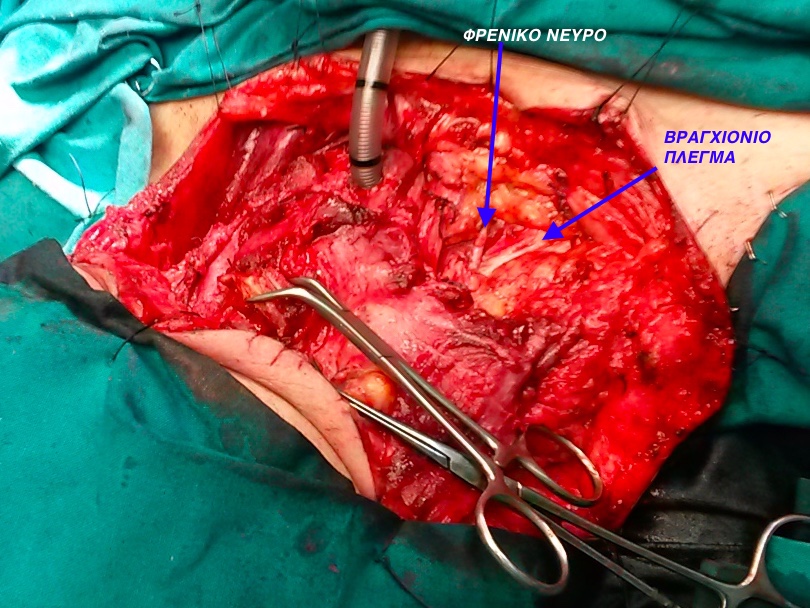

Το χειρουργείο για τη μερική ή ολική λαρυγγεκτομή, πραγματοποιείται υπό γενική αναισθησία πάντα. Αρχικά, γίνεται μία τομή στον λαιμό και, στη συνέχεια, αφαιρείται ολόκληρος ο λάρυγγας ή μέρος αυτού, ενώ σε ορισμένες περιπτώσεις μπορεί να αφαιρεθεί και μέρος από τον φάρυγγα ή και οι λεμφαδένες (Λεμφαδενικός Καθαρισμός Τραχήλου) Λεμφαδενικός Καθαρισμός Τραχήλου . Το επόμενο βήμα είναι η δημιουργία μιας στομίας (τρύπας) στον λαιμό, μπροστά, και ενός ανοίγματος στην τραχεία η οποία προσκολλάται στην τρύπα που έχει δημιουργηθεί, από όπου θα αναπνέει ο ασθενής μετά τη λαρυγγεκτομή (τραχειοστομία).

Θα ακολουθήσει η παράθεση κάποιων περιστατικών μου

Περιστατικό 1

Περιστατικό 2

Περιστατικό 3

Περιστατικό 4

Περιστατικό 5